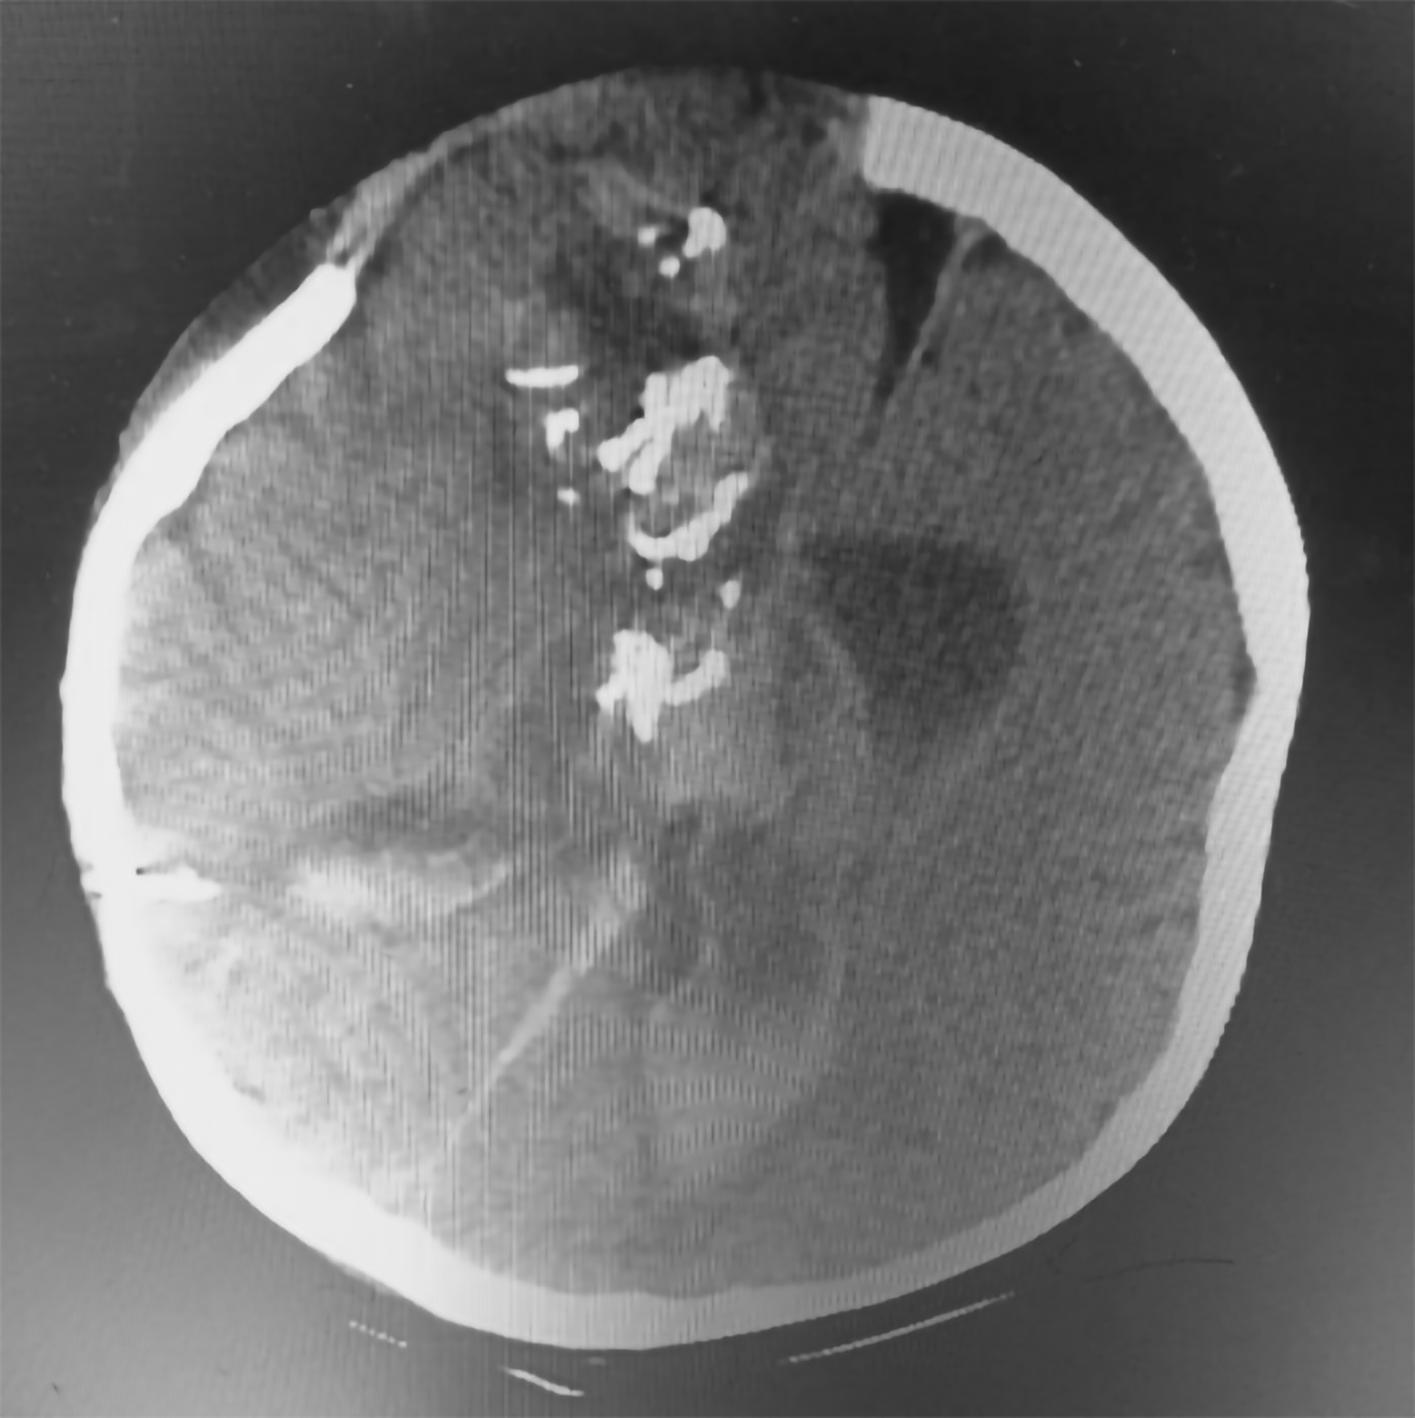

Tumor removal was performed through a transfrontal transcortical transventricular approach towards the 3rd ventricle. We aimed for gross total tumor removal and found a multiloculated solid cystic mass with thick glistening greyish content attached to the septum pellucidum and bilateral fornix. Massive bleeding occurred upon removal of the tumor from the bed, and we suspected that the internal cerebral vein was injured. The patient lose almost 1.5 L of blood and suffered from hemorrhagic shock during fluid resuscitation and blood transfusion were being given. We packed the bleeding with cotton patties, and the surgery was stopped for salvage. The patient was sent to the pediatric ICU for stabilization, knocked down for three days, and regained consciousness. Another CT scan revealed intraventricular hemorrhage (Figure 3). We performed another craniotomy to remove the hemostasis pack 10 days later. Histopathological examination revealed a mature teratoma consisting of flat epithelial cells, fat cells, cartilage, chondrocytes, and ciliated pseudostratified epithelial cells (Figure 4). The patient was discharged one week after the 2nd craniotomy. The postoperative CT scan revealed a small remaining intraventricular tumor and hydrocephalus; therefore, another VP shunt was placed on the contralateral side (Figure 5). After surgery, the patient had a GCS score of 15, but the developed left hemiparesis. The clinical timeline is shown in Figure 6.